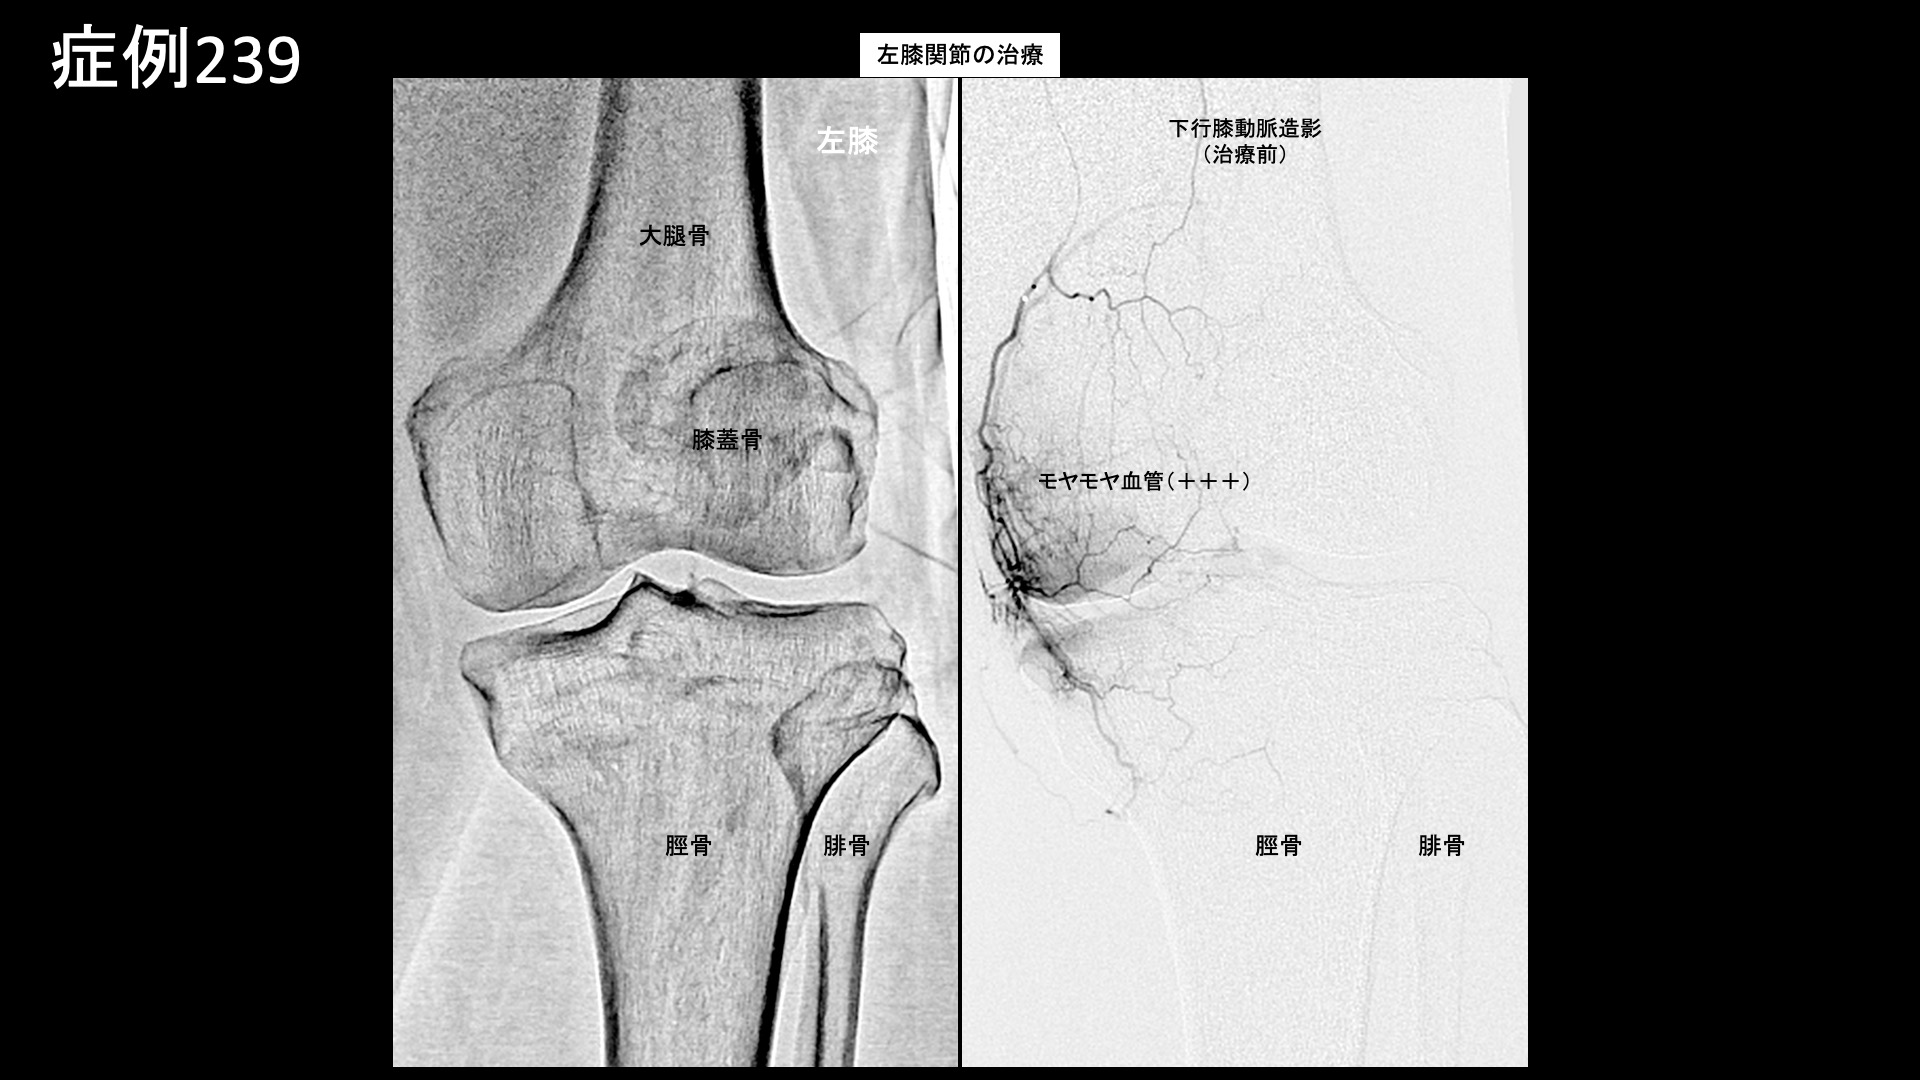

膝:変形性膝関節症など 【70代:男性】夜間痛がその日のうちに改善!強い炎症を伴った変形性膝関節症に対する運動器カテーテル治療(変形性膝関節症) 2025.09.23 鴨井院長による動画解説 受診までの経過 半年前から右膝が痛むようになりました。夜間に疼くようにもなったため、当院を受診しました。 診察時の所見 レントゲンでは両膝関節に中等度以下の変形が見られました(KL分類2/4程度)。両足は扁平足でした。エコーでも同様に中等度までの変形にとどまっていましたが、一方で、異常血流信号は非常に旺盛にみられ、強い炎症が示唆されました。 良い治療適応と判断し、モヤモヤ血管(病的新生血管)に対する運動器カテーテル治療(微細動脈塞栓術)を受けていただきました。 治療の所見 血管造影を行うと、左右とも全周性にモヤモヤ血管が濃染像として描出されました(写真は、下行膝動脈、内側下膝動脈、外側下膝動脈の各血管造影について掲載)。やはり、強い炎症を反映した所見でした。治療後は画像上速やかに消失しました。 治療後の経過 治療直後から症状が改善し、ほぼ痛みが無くなりました。帰り道にも既に違いを実感し、その日の夜にはいつもじんじんと疼いていた痛みが無くなっていました。治療後1ヶ月の再診時には、奇跡的に良くなっている、こんなにも良くなるものかと驚かれました。これまでと人生観が変わり、何か新しいことを初めてみようかと思えるようになったと言われました。その後も違和感を生じることはあるものの、痛みが再燃することはありませんでした。治療後3ヶ月でも順調に経過されており、終診としました。 通常の変形性膝関節症ではもう少し時間をかけて改善することが多いのですが、非常に早期から改善しました。モヤモヤ血管(病的新生血管)に対する運動器カテーテル治療(微細動脈塞栓術)は、炎症が強いほど早期から改善が得られる傾向がありますが、まさにそうした症例でした(夜間痛も強い炎症を反映した臨床所見の一つです)。まだ変形が高度に進行していない内に治療を受けていただけたことも、良い結果が得られた要因です。カテーテル治療の強みを最大限に生かすためには、高度の変形にまで進行する前にご検討いただくとよいと思います。 膝の痛みについては、何とか歩けるうちは医療機関を受診しないという方も多く、受診を決断した時には既に変形が高度に進行していたということも少なくありません。変形性関節症は進行性の病気であり、加齢によっても進行しますが、進行するほど種々の治療が効きにくくなってしまいます。ある程度までの状態でしっかりと治し、その後の進行を予防するための靴・インソール調整、筋力トレーニングなどに取り組み、日常生活についても指導を受けた方が、結果的には長く自分の足で健康に歩くことができますので早めに対処していただくことをおすすめします。昨今では、レントゲンに加えてMRI検査まで受けずともエコー検査である程度の詳細な状態を把握することができますし、そうした医療機関が増えてきています。エコー検査は気軽に受けられますので、状態に応じて、時々チェックを受けるのも良いと思います。 変形性膝関節症の詳しい病状説明はこちら 【80代:女性】新型コロナウイルス感染を契機に悪化した変形性腰椎症による腰痛/坐骨神経痛(新型コロナウイルス感染、変形性腰椎症、腰痛、坐骨神経痛) 前の記事 【10代:男性】恥骨が痛くて走れない、スポーツが原因で生じた恥骨結合炎に対するモヤモヤ血管治療(恥骨結合炎) 次の記事